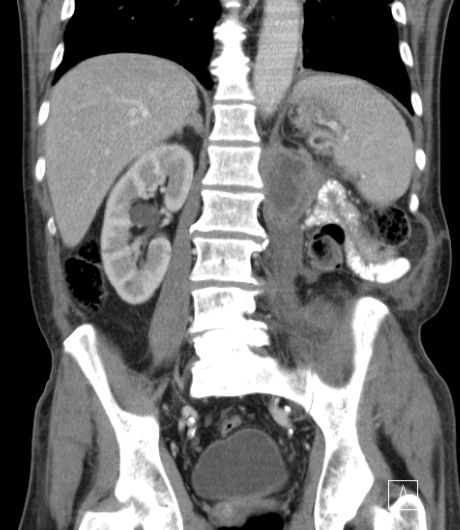

61-jähriger Mann bei dem notfallmäßig eine Tumornephrektomie links wegen Sepsis und nekrotisch zerfallendem, infiziert rupturiertem NZK links cT3b pM0 M0 G2 durchgeführt wurde. Makroskopie: 15 x 9 x 10 cm großes Nephrektomiepräparat. Im Zentrum überwiegend im Hilusbereich entwickelt, ein stark nekrotisch zerfallender, 8 cm großer Tumor.

Mikroskopie: Der Tumor zeigt papilläre, teilweise tubuläre Strukturen.

Die Einzelzellen enthalten vergrößerte hyperchromatische Zellkerne mit prominenten Nukleolen.

Das Zytoplasma ist teilweise klar, teilweise schwach eosinrot angefärbt.

Teilweise erkennt man Tumoranteile mit girlandenförmigen Proliferaten.

Immunhistochemie: z.T positiv mit CD 10. Herdförmig kräftig positive Reaktion mit Zytokeratin 7 und Vimentin. CD 117, Melan A und HMB 45 negativ.

5 Monate später Rezidiv. Th.:Pazopanib